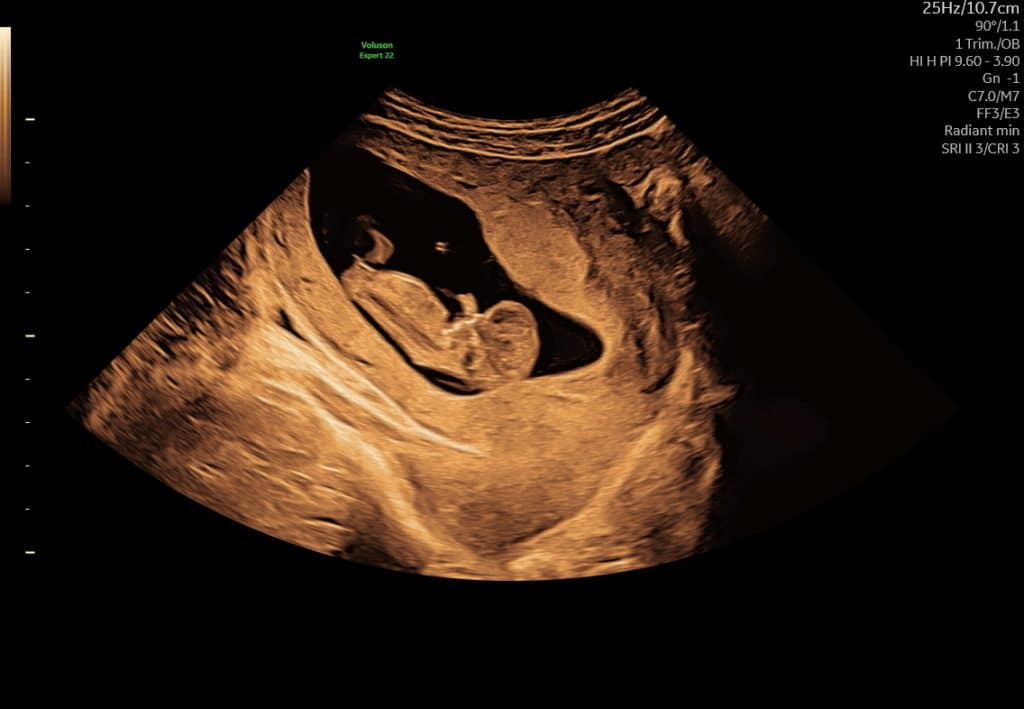

Ultralydsscanning uge 7 hjerteblink

Ultralydsscanning uge 8 lille foster i livmoderen

Eksempel på ultralyd i uge 7–8. Hjerteblink kan ofte ses, men synligheden varierer.

I denne periode kan bevægelse ofte ses tydeligere på video end på stillbilleder.

Kort ultralydssekvens fra uge 7, hvor hjerteaktivitet og tidlig bevægelse kan ses